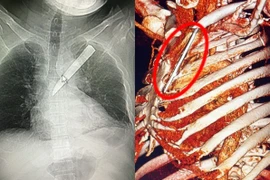

Cha mẹ cần tránh để trong tầm với của trẻ những đồ vật dễ làm tổn thương trẻ như ghim băng, khung nhựa, đinh vít… Cha mẹ cũng nên loại bỏ hết xương, hạt trước khi cho trẻ ăn các loại thức ăn có xương hoặc các hoa quả có hạt.